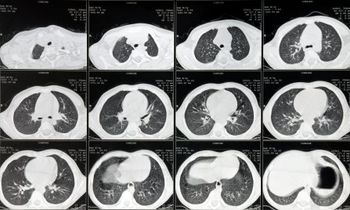

A 39-year-old woman presents with dyspnea and cough. A bronchial mass in found. What is your diagnosis?

A 51-year-old man presents with a lung mass. What is your diagnosis?